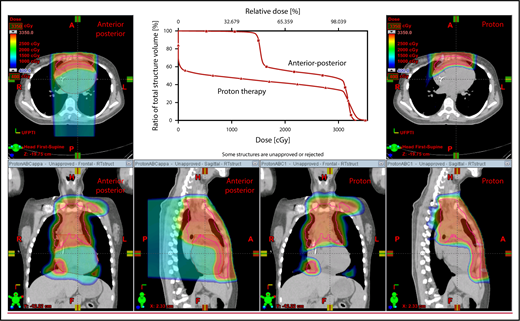

A 4D CT scan can help to establish the extent of respiration-induced anatomic motion and the appropriate ITV expansion. However, this introduces an additional uncertainty; to mitigate the latter, the radiation volume has to be increased. Thus, use of DIBH is ideal to reduce the motion of the mediastinum and its respiration-dependent change in shape (thinner during inspiration, wider during free breathing) (Figure 7).59 It is accomplished by acquisition of the anatomical data in a fixed respiratory phase. DIBH can have the additional benefit of displacing the heart inferiorly, as well as expanding the lungs away from the target, potentially reducing the dose received by these OARs.

Use of DIBH can help to manage some of the uncertainties associated with the use of proton therapy. Compared with free breathing (right panel), DIBH expands the lungs, moves the heart downward, and causes the mediastinum to become thinner (left panel).